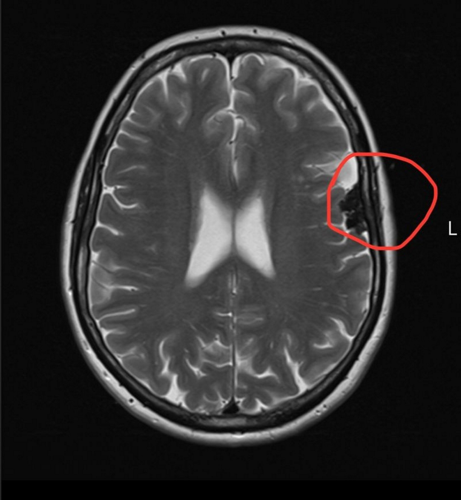

A late night MRI revealed a meningioma, a type of , and five months later, after waiting for specialists to get back to her, she was told she had two brain tumors.

The tumors are now being monitored with regular MRI's.